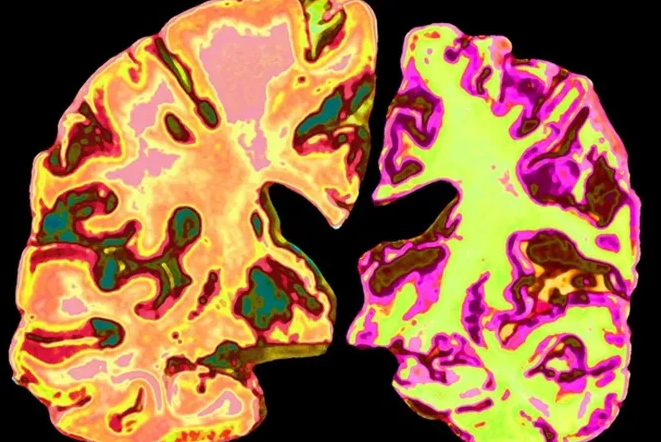

Срез нормального человеческого мозга (слева, искусственно окрашен) контрастирует со срезом мозга человека с болезнью Альцгеймера. Jessica Wilson/Science Photo Library